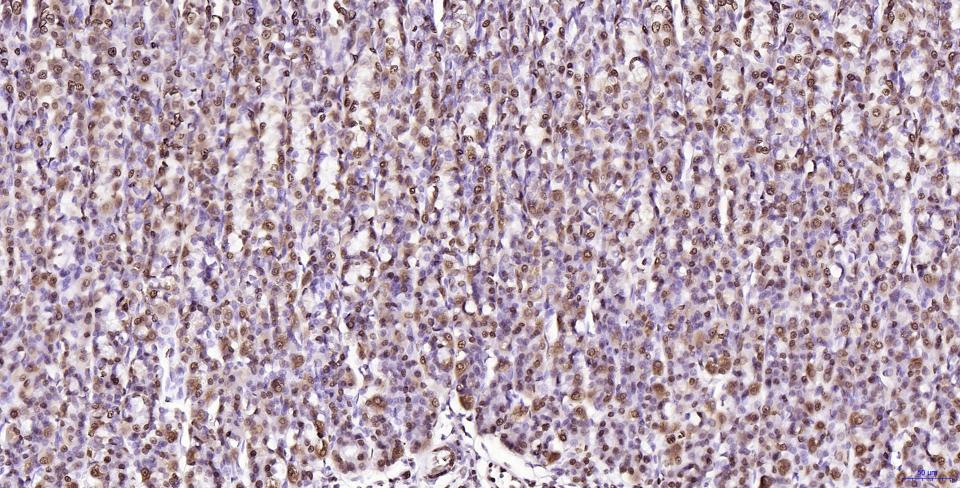

Paraformaldehyde-fixed, paraffin embedded Human Kidney; Antigen retrieval by boiling in sodium citrate buffer (pH6.0) for 15 min; Antibody incubation with Histone H2A.X Monoclonal Antibody, Unconjugated(bsm-61080R) at 1:200 overnight at 4°C, followed by conjugation to the SP Kit(Rabbit, SP-0023) and DAB (C-0010) staining.

Paraformaldehyde-fixed, paraffin embedded Human Colon Cancer; Antigen retrieval by boiling in sodium citrate buffer (pH6.0) for 15 min; Antibody incubation with Histone H2A.X Monoclonal Antibody, Unconjugated(bsm-61080R) at 1:200 overnight at 4°C, followed by conjugation to the SP Kit(Rabbit, SP-0023) and DAB (C-0010) staining.